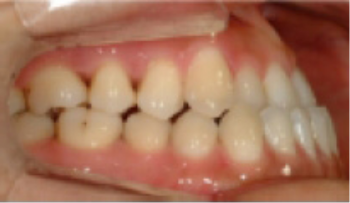

• 상악 전돌(돌출) 위턱이 앞으로 나옴.

Before

After